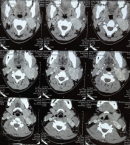

Diagnostic assessment: a contrast-enhanced cervical CT scan showed an intensely enhancing soft tissue within the left carotid sheath, which splays the internal and external carotid arteries, producing the characteristic ''lyre'' appearance on sagittal reconstructed views. Complete encasement of the common carotid artery and internal jugular vein was noted at the C2-C4 vertebral levels. A magnetic resonance angiogram of the neck showed a T2-weighted hyperintense mass at the left carotid bifurcation measuring 3.4 x 2.6 x 4.3cm. Multiple flow voids were seen in the mass, causing displacement of the left external and internal carotid arteries.

CBTs are often detected incidentally during physical examination or imaging. Diagnostic evaluation includes Doppler ultrasonography, CT, magnetic resonance angiography, and digital subtraction angiography (DSA). A CT Scan was done for our patient, showing the mass (Figure 3). DSA remains the gold standard, characteristically demonstrating splaying of the internal and external carotid arteries (Lyre sign). However, colour Doppler ultrasonography provides a reliable, non-invasive alternative with high sensitivity and specificity [3,7]. Preoperative biopsy is contraindicated due to the risk of massive haemorrhage, pseudoaneurysm formation, tumor seeding, and carotid thrombosis [3] (Figure 4).

Figure 3: computed tomography angiography of the neck showing the carotid body tumor and its relationship with the internal and external carotid arteries